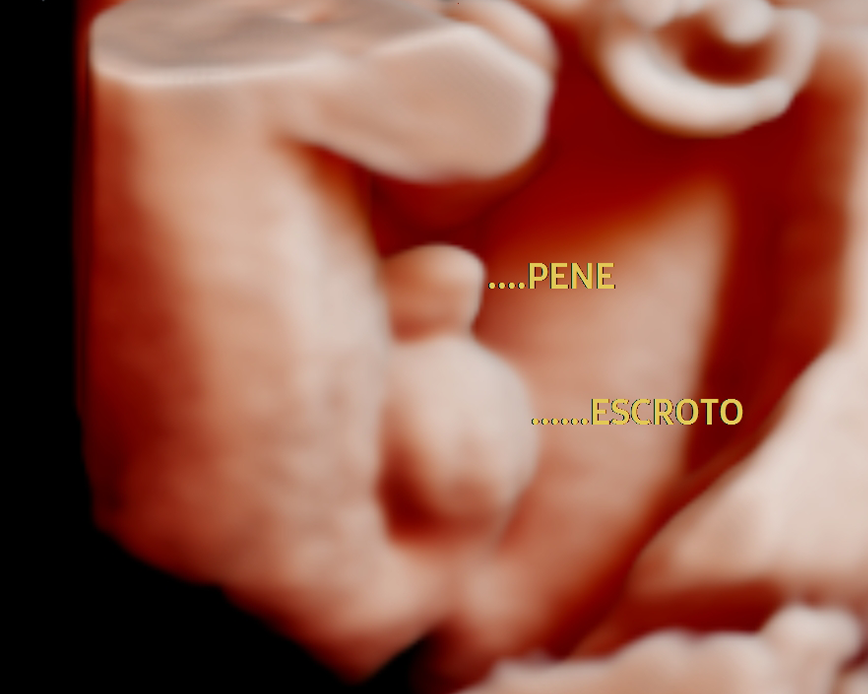

Esta ecografía permite identificar el sexo del bebé con precisión a partir de la semana 12 de gestación. Además, ofrece información sobre el bienestar fetal, la ubicación de la placenta y la cantidad de líquido amniótico, asegurando el monitoreo adecuado del embarazo.

Esta ecografía permite identificar el sexo del bebé con precisión a partir de la semana 16 de gestación. Además, ofrece información sobre el bienestar fetal, la ubicación de la placenta y la cantidad de líquido amniótico, asegurando el monitoreo adecuado del embarazo.